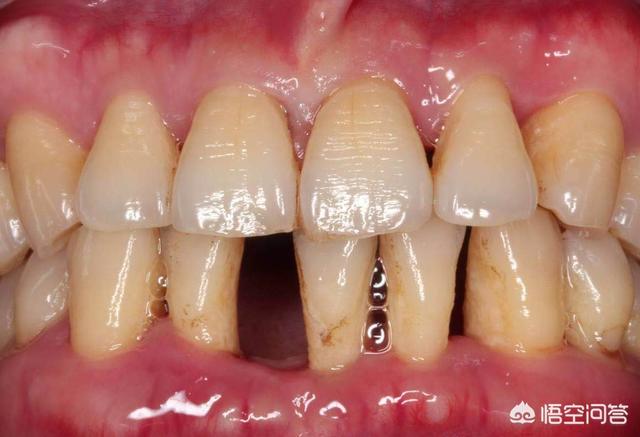

2. le déchaussement des dents causé par la parodontite

Si, pour certaines raisons, la parodontite affecte non seulement le tissu gingival, mais aussi les fibres de la membrane parodontale, la cavité buccale de diverses bactéries attaque directement les tissus parodontaux, et la parodontite exacerbe à son tour la récession des gencives, ce qui forme un cercle vicieux, détruisant non seulement les gencives, mais affectant également la fermeté des dents, ce qui conduit au déchaussement des dents.

En outre, si le tissu parodontal subit des changements dégénératifs, il est également sujet à la destruction des fibres parodontales ou à la résorption de l'os alvéolaire, ce qui peut entraîner le déchaussement des dents.

Manifestations cliniques : Outre le déchaussement des dents, il peut s'accompagner d'une congestion, d'une rougeur et d'un gonflement des gencives, de la formation de poches parodontales et, dans les cas les plus graves, de la formation d'abcès.

2. la parodontite

Les patients atteints de parodontite présentent des degrés divers de déchaussement des dents en raison de la perte des tissus de soutien parodontaux et de la résorption de l'os alvéolaire englobant la racine de la dent, avec la possibilité de perdre la dent dans les cas graves de résorption de l'os alvéolaire.